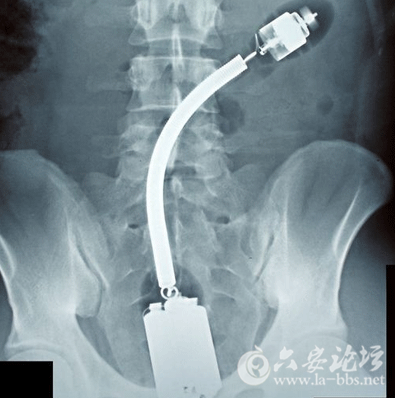

这些让人瞠目结舌的X光片,映射出了女人下体的那点儿事儿,对性有需求是好的,可是要是乱放东西,伤到身体,那可麻烦大了!

告诉我,这不是一根带着尾巴的震动棒!这种深度,难道是进入卵巢了?